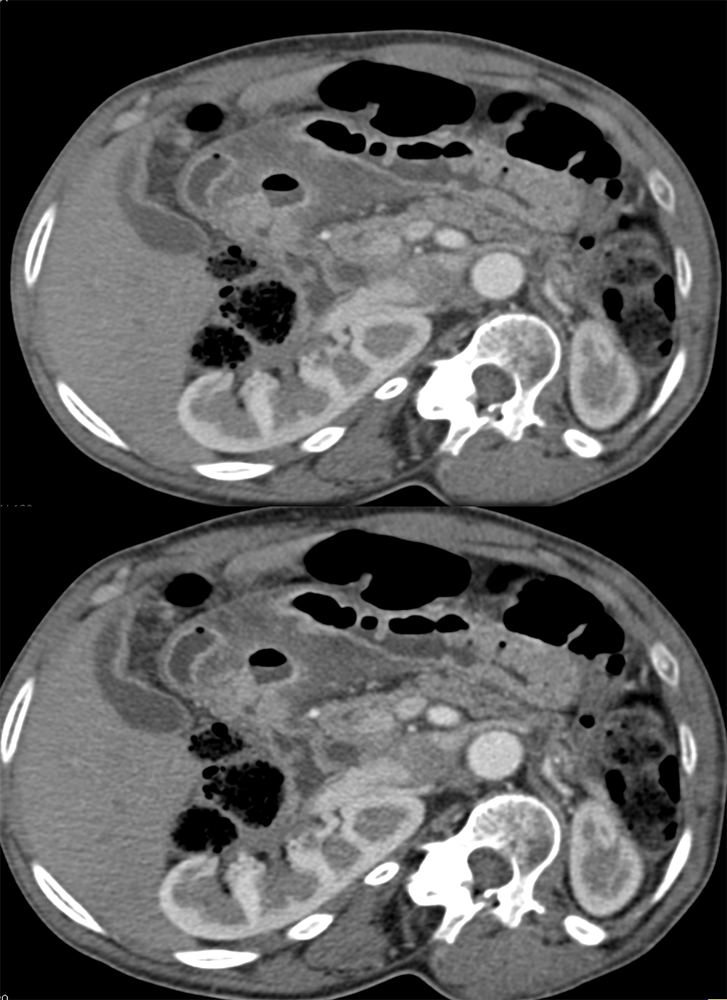

“Gastritis can be secondary to many etiologies including infection, systemic illness such as trauma or burns, and autoimmune disease. Peptic ulcer disease is most commonly caused by Helicobacter Pylori infection and chronic NSAID use . The most common sites for ulcer formation are the gastric antrum/pylorus and proximal duodenum. The resultant edema and fibrosis around the ulcer site can cause narrowing and eventual obstruction of the gastric outlet [9]. Prior to the widespread use of H2 blockers and proton pump inhibitors, peptic ulcer disease was the most common cause of gastric outlet obstruction, however in the era of H2 blockers, outlet obstruction now predicts malignancy. While endoscopy is the modality of choice for diagnosing gastritis, CT is often performed first particularly in the setting of acute abdominal pain.” Imaging of acute gastric emergencies: a case-based review Jetty S et al. Clinical Imaging 72 (2021) 97–113 |

“On imaging, it can be difficult to distinguish benign peptic ulcer disease from malignant causes of gastric outlet obstruction and biopsy is required for confirmation. Peptic ulcers can perforate and should be recognized on imaging.” Imaging of acute gastric emergencies: a case-based review Jetty S et al. Clinical Imaging 72 (2021) 97–113 |

“On CT, gastritis will appear as wall thickening with alternating hyper- and hypoattenuation representing mucosal enhancement and submucosal edema. The presence of mucosal enhancement (hyperemia) on CT suggests gastritis as the cause of gastric wall thickening. An uncommon form of gastritis is emphysematous gastritis. It is usually caused by gas-forming Escherichia coli. Initially obtained AXR may show mottled gas outlining the gastric wall. CT can confirm the diagnosis. Mottled gas can also be a sign of gastric pneumatosis from ischemia.” Imaging of acute gastric emergencies: a case-based review Jetty S et al. Clinical Imaging 72 (2021) 97–113 |